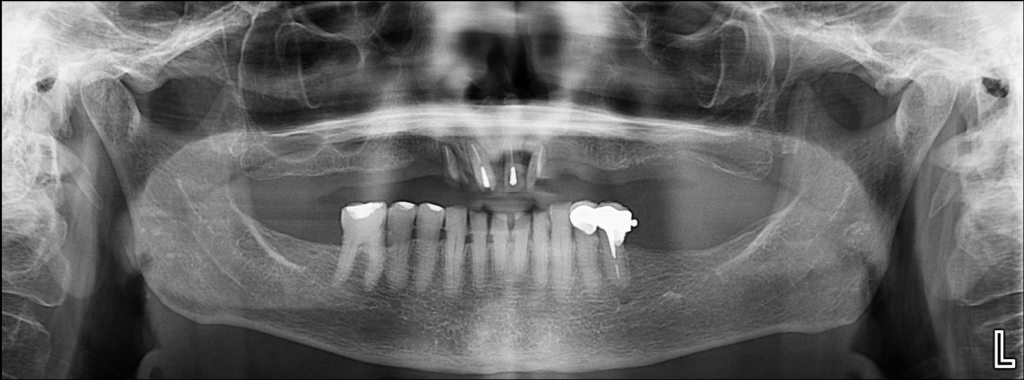

Radiografia Panorámica

En la radiografía panorámica se observan edentulismo parcial superior e inferior, placa cervical mineralizada generalizada, dispositivo de retención protésica en pieza 35, remanentes radiculares de piezas 32, 31, 41 y 42 con obturación de conductos.